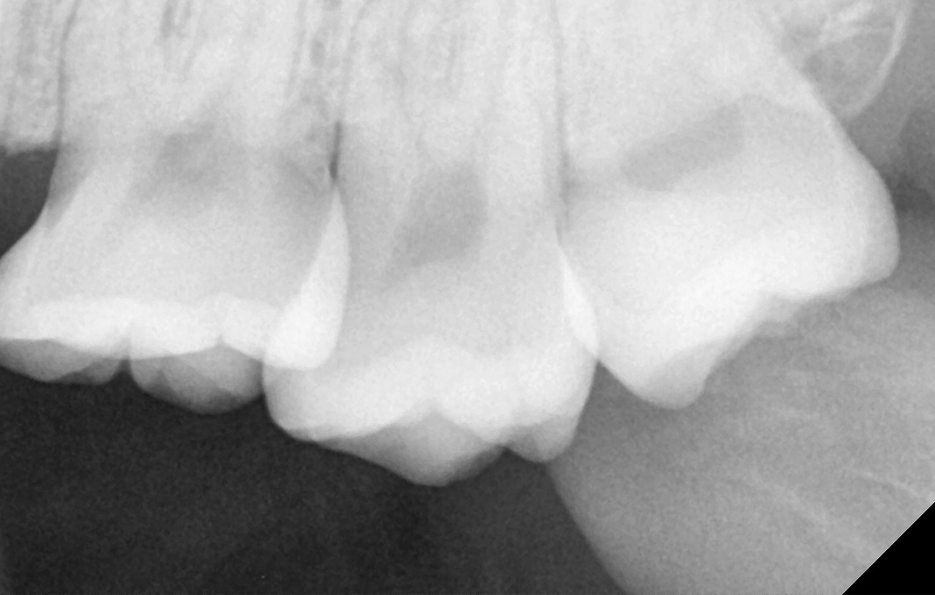

부분적으로 맹출된 사랑니는 어금니와 사랑니 사이에 음식물이 끼기 쉽고 어금니 인접면에 사랑니로 인한 충치가 발생되기도 쉬우며 심한 경우에는 어금니의 뿌리 쪽 손상을 일으켜서 신경치료나 발치까지도 이르게 되는 경우가 있기 때문에 사랑니 발치 시점을 놓치게 되면 어금니 손상까지 커질 우려가 있어요

사랑니발치통증 줄이기 위해서는 기본적으로 사랑니 혹은 사랑니 주변의 청결관리가 잘 안되는 것을 느끼는 초기에 발치를 하는 것이 수월하며 사랑니의 문제가 어금니나 주변 잇몸으로 영향을 주기 전에 발치를 계획하는 것도 더 큰 고생을 하지 않을 수 있는 방법이 될 거예요